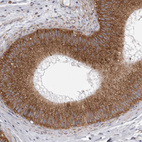

Immunohistochemistry analysis in human epididymis and skeletal muscle tissues using HPA027883 antibody. Corresponding CDK5RAP3 RNA-seq data are presented for the same tissues.